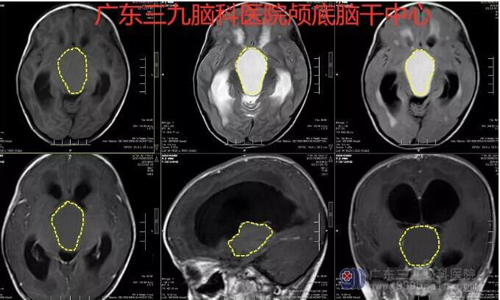

图2:鞍上池内可见一类圆形等T1长T2异常信号影,FLAIR序列呈明显高信号,边界清晰,范围约为5.7×4.4×3.7cm,病灶内可见斑片状各序列偏低信号影;增强扫描呈边缘线样强化,病灶内可见斑片状轻度强化影。视交叉显示不清。双侧侧脑室旁-半卵圆中心示大片状长T1长T2异常信号影,FLAIR序列呈高信号;胼胝体膝部示T2WI极低信号。脑实质、脑干受压,脑回变细,幕上脑室系统扩张,脑沟、脑裂示多发线样异常强化影,中线结构居中。矢状位示垂体受压变扁;小脑脑沟、脑裂增宽。